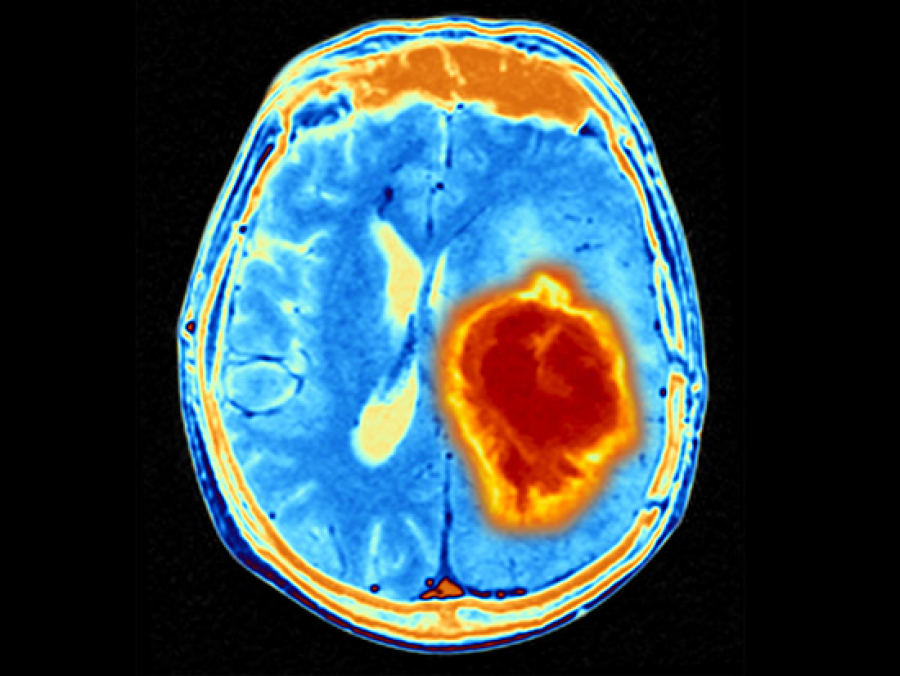

G207, an immunotherapy derived from a modified herpes virus is well tolerated in children with gliomas, and shows signs of clinical effectiveness

This new, non-invasive way to deliver radiation has helped one Alabama man complete optometry school and launch his new career.

UAB neurologists have reported the first case study of a patient with a brain bleed linked to consumption of an energy drink.